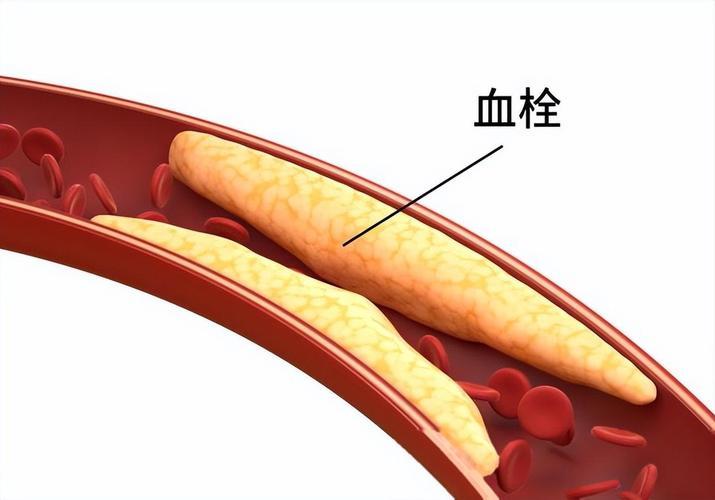

来看看心脏血管斑块破裂是什么样子的。一个 75 岁的男性患者,在医院就诊时,突发心脏骤停倒地,经胸外按压积极抢救后恢复意识。 紧急做了冠状动脉造影,发现是前降支中段一个不稳定斑块出现的破裂,局部有血栓形成。这就是导致患者突发意识丧失的原因。导丝通过前降支病变后,植入支架三枚,把斑块附近的有动脉硬化的血管全部覆盖,血流恢复通畅。 其实这里的狭窄本身并不严重,狭窄程度大约在 70% 左右。突然出现急性心肌梗塞,并不是说堵塞非常严重,而是一些不稳定的斑块突然破裂,导致的局部血栓形成,进而堵塞整个血管。 冠心病的治疗,一方面是预防血栓,另外一方面是尽量稳定动脉硬化斑块,让其不容易破裂。稳定斑块的方法,最主要的是降低低密度脂蛋白胆固醇,一旦发现有冠心病,最好把低密度脂蛋白胆固醇降低到 1.8 以下,最好降低到 1.4 以下。这样斑块才会更加稳定,不容易破裂,也就不容易突发急性心肌梗塞了。